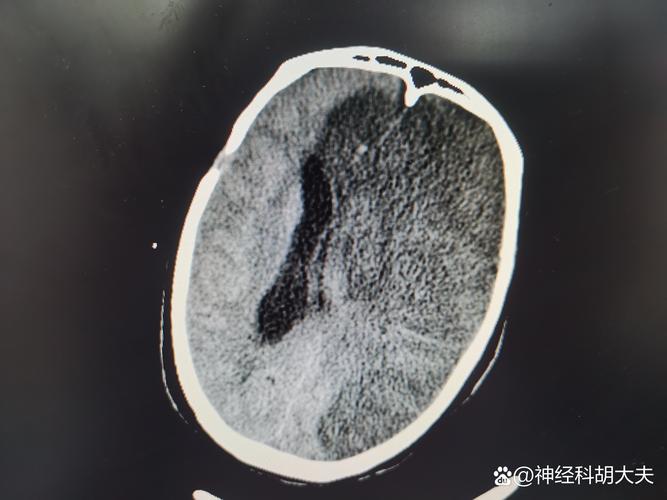

- 什么是腔隙性? 这种梗死灶非常小,通常直径在1.5-3毫米之间,它发生在大脑深部的一些特殊小动脉供血的区域,这些小动脉像树枝的末梢,一旦堵塞,影响的范围就很小,形成一个“腔隙”样的病灶。

- 腔梗是缺血灶的一种,腔梗是已经发生了坏死的、陈旧的缺血灶,在影像上表现为一个明确的“小洞”。